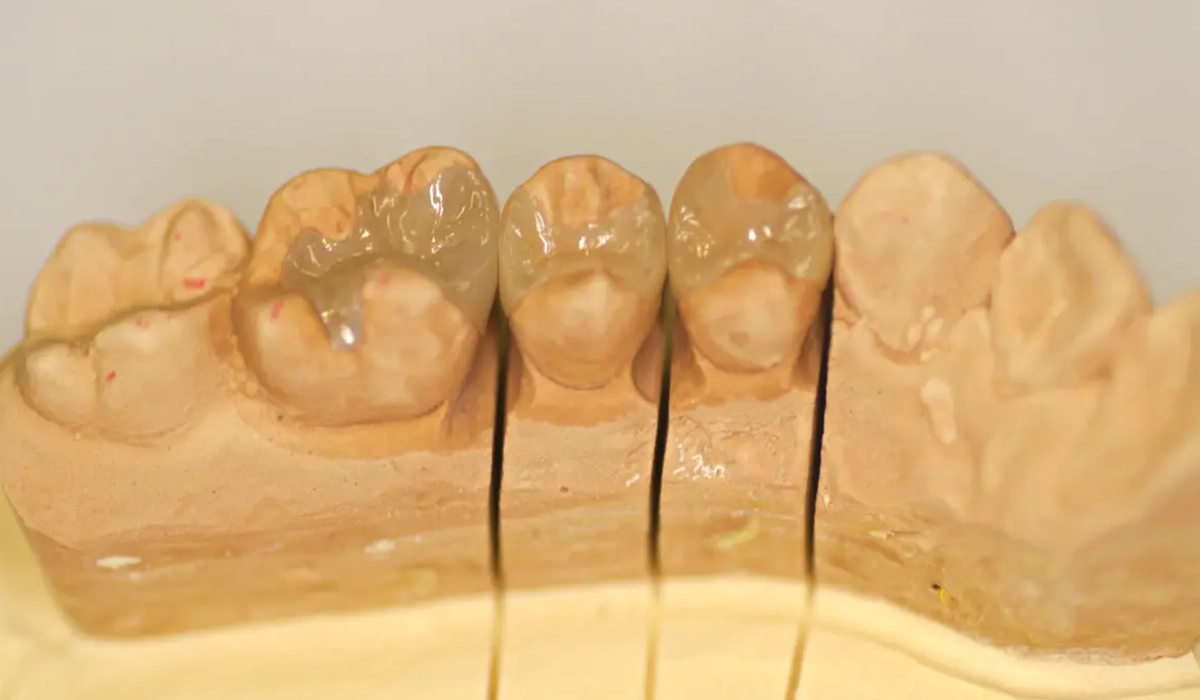

精密な型取りで模型づくり

お口の中にはいる歯の素材だけこだわっていても、実は片手落ちです。

虫歯を除去した歯は、お口の中の「型」を取り、それを元にお口の中を再現した「石こう模型」を作ってつめものやさし歯を作ります。

その型取りをする際に使用する材料は主に2つあります。

アルジネート印象材とシリコン印象材です。

アルジネート印象材は、一般的にどの歯科医院でも昔から使用されているピンクの冷たい材料です。コストパフォーマンスに優れ、実用上は問題がありませんが、 アルジネートは変形しやすい欠点があり、短時間で形が変わり始めるため、精密性に劣ります。

一方、シリコン印象材はゴムでできており、型取り後ほとんど変形しないため、長期間歯の形をそのまま保存してくれるとても優れた材料です。

ですが、アルジネート印象材に比べてかなり高価ですので(材料費は10倍以上します)、保険治療では使用することができません。

セラミック治療の際は、シリコン印象材を使用し、より精密な治療を行う事ができます。